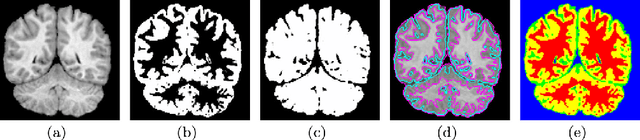

Abstract:Multiphase active contour based models are useful in identifying multiple regions with different characteristics such as the mean values of regions. This is relevant in brain magnetic resonance images (MRIs), allowing the differentiation of white matter against gray matter. We consider a well defined globally convex formulation of Vese and Chan multiphase active contour model for segmenting brain MRI images. A well-established theory and an efficient dual minimization scheme are thoroughly described which guarantees optimal solutions and provides stable segmentations. Moreover, under the dual minimization implementation our model perfectly describes disjoint regions by avoiding local minima solutions. Experimental results indicate that the proposed approach provides better accuracy than other related multiphase active contour algorithms even under severe noise, intensity inhomogeneities, and partial volume effects.